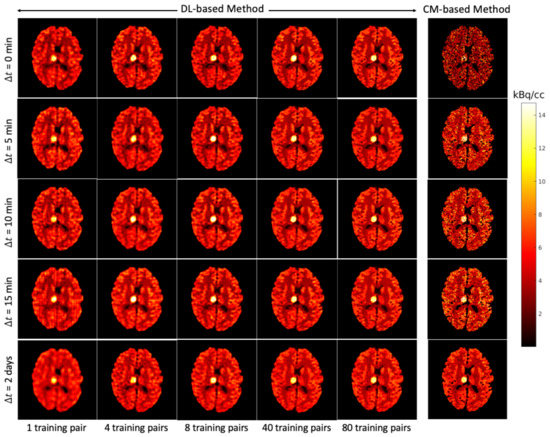

3.2. Implementation of Deep-Learning-Based Dual-Tracer Separation Method

The simulated brain phantoms were reconstructed using the classic maximum-likelihood expectation maximization (MLEM) algorithm [58]. A total of 128 iterations were used for EM reconstruction to maintain the balance between bias and noise as suggested in [28,59]. Given that the PET scanner measures average activity concentration over time, the reconstructed dynamic dual-tracer images were further normalised by frame widths, e.g., for the mth frame, to obtain the (non-decay corrected) dual-tracer TACs of each voxel. The reconstructed single-tracer images were also normalised by 20 min static acquisition time to obtain the activity distributions. The reconstructed dynamic dual-tracer images and the reconstructed static single-tracer images were used as network inputs and training labels, respectively. Examples of reconstructed static single-tracer noisy MLEM images are shown in Figure 6c,f, together with the corresponding noise-free MLEM reconstructions (NF) (b,e) and the ground truths (a,d). When 2 days, the dual-tracer signals were entirely separated (reasons for which are discussed in Section 3.1), and thus two reconstructed dynamic single-tracer images were obtained, one for each tracer. In this case, the reconstructed dynamic single-tracer images (either FDG or MET) were employed as the network input. In this special case, the MSE loss is only applied to either FDG or MET, depending on the choice of the tracer considered in the network input. Notice that the decay correction cannot be performed in dual-tracer PET prior to separation because the proportion of each tracer (and hence its decay correction factor) is unknown prior to separation. While we do model decay, we do not seek to include decay correction in this present work.

Figure 6.

Brain phantom: an example of the simulated static single-tracer images (tracer activity distributions) for and : (a,d) ground-truth static images; (b,e) noise-free MLEM reconstructions; (c,f) noisy MLEM reconstructions.